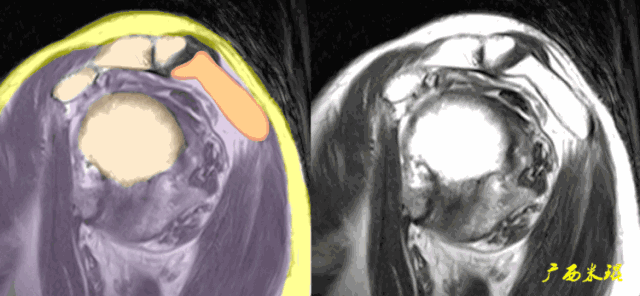

(2)斜矢状位:垂直于冈上肌长轴,观察肩峰形态及喙肩弓,观察肩袖4个组分的短轴断面。

(3)平行于关节盂/垂直于盂肱关节,主要评估盂唇,同时兼顾肩胛下肌、冈下肌及小圆肌。

c.钩状肩峰,发生肩袖撕裂的机会大,但绝不是百分之百。

d.肩峰骨刺,发生肩袖撕裂的机会比钩状肩峰还要大,必须认真阅看,肩峰骨刺在斜矢状位上显示得非常清楚。

肩峰骨刺在斜冠状位上能够看到,应该认真观察并且留意其对应的肩袖面。

e.肱骨大结节骨赘增生,一般是较久的反复的撞击造成,一旦出现,肩袖撕裂的可能性极高。

f.肱骨大结节部位的皮质骨下囊肿,也是长时间撞击的一种表现,不但是肩袖撕裂重要的间接征象,也是肩袖撕裂手术治疗的一个难点。

g.肱骨大结节的部分缺损是长时间严重撞击的表现,在斜冠状位发现缺损的同时,一般都能看到肩袖的中断和回缩。